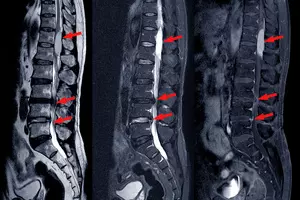

허리 협착증은 척추 전체의 척추관이 좁아지는 척추관 협착증의 하위 개념으로, 특히 허리 부위의 척추관이나 추간공이 좁아져 척수와 신경이 압박되는 질환입니다. 척추관은 척추뼈 내부를 통과하는 통로이며, 추간공은 척추뼈 사이에 있는 공간입니다. 60대 이상의 노년층에게 흔하게 발생하지만, 어린 나이에도 발생할 수 있습니다. 허리 협착증은 허리보다는 다리 통증이 심한 경향이 있으며 다리가 무겁거나 저린 느낌이 들며, 근력이 약해지는 등의 증상을 유발합니다.